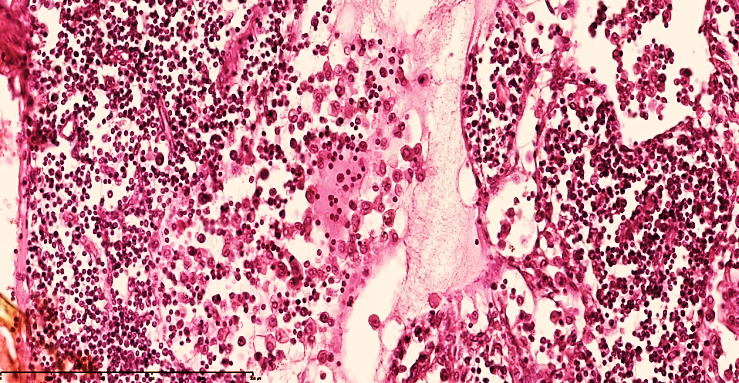

Lymphostasis and dilatation of lymphatic capillaries are preserved in the lymph nodes. In the subcapsular area of the lymph node, a small number of macrophages and lymphocytes are detected in the spaces where the cyst has expanded. Areas of regenerating V-lymphocytes in the cortical area are defined, although the lymphoid follicular boundaries and texture are uneven (see Fig. 4). | Figure 4. Mesenteric lymph node of a 28-day-old infant with peritonitis. Treated on the 6th day. Macrophages increased in the peritrabecular area, lymphocytes and plasma cells decreased, and oligonucleated lymphoblasts increased, and stroma was found to be disrupted. Vascular dilation and collapse were detected. Staining G.E. Size 40x10 |

In the paracortical areas, a small number of T-lymphocytes are found, and in the space around the vessels, destroyed and various cell fragments are found. This fluid moves directly to the regional lymph nodes. The lymph node capsule is tense, of uniform thickness, macrophages are relatively reduced in the subcapsular space, lymphocytes are detected.Postcapillary venules were full-blooded, with foci of free lymphocyte migration in the focus. The perimeter of the postcapillary venules was covered with fibrinoid thickening.It was found that the histiotopographic shape of the lymph node was deformed in the areas of thickening and destruction of the trabecular stroma components, and the morphofunctional parameters of the lymph node were out of whack.Lymphostasis in the lymph nodes, lymphothrombosis, lymphadenitis in the lymph nodes, delymphatization and the development of foci of neutrophil infiltration in the postcapillary venules, complete blockage of the lymphatic drainage system in the lymph node, leading to the development of secondary complications (sepsis, septicemia, septicopyemia, etc.).Degranulation of mast cells in the microcirculatory bed, as a result of which plasmorrhagia and leukodiapedesis are enhanced, leading to the formation of inflammatory infiltrates in the parietal and visceral layers. (See Fig. 5, 6). As a result, venous congestion occurs, which leads to the development of interstitial edema and a sharp functional strain of the drainage system in the lymph nodes, which leads to lymph node enlargement and lymph node edema (See Fig. 7). | Figure 5. Mesenteric lymph node of a 28-day-old infant with peritonitis. In the cortical area, lymphocytes and plasma cells are reduced, lymphoblasts are increased with nucleoli, and stroma is disrupted. Delymphatic foci are detected. Staining G.E. Size 40x10 |